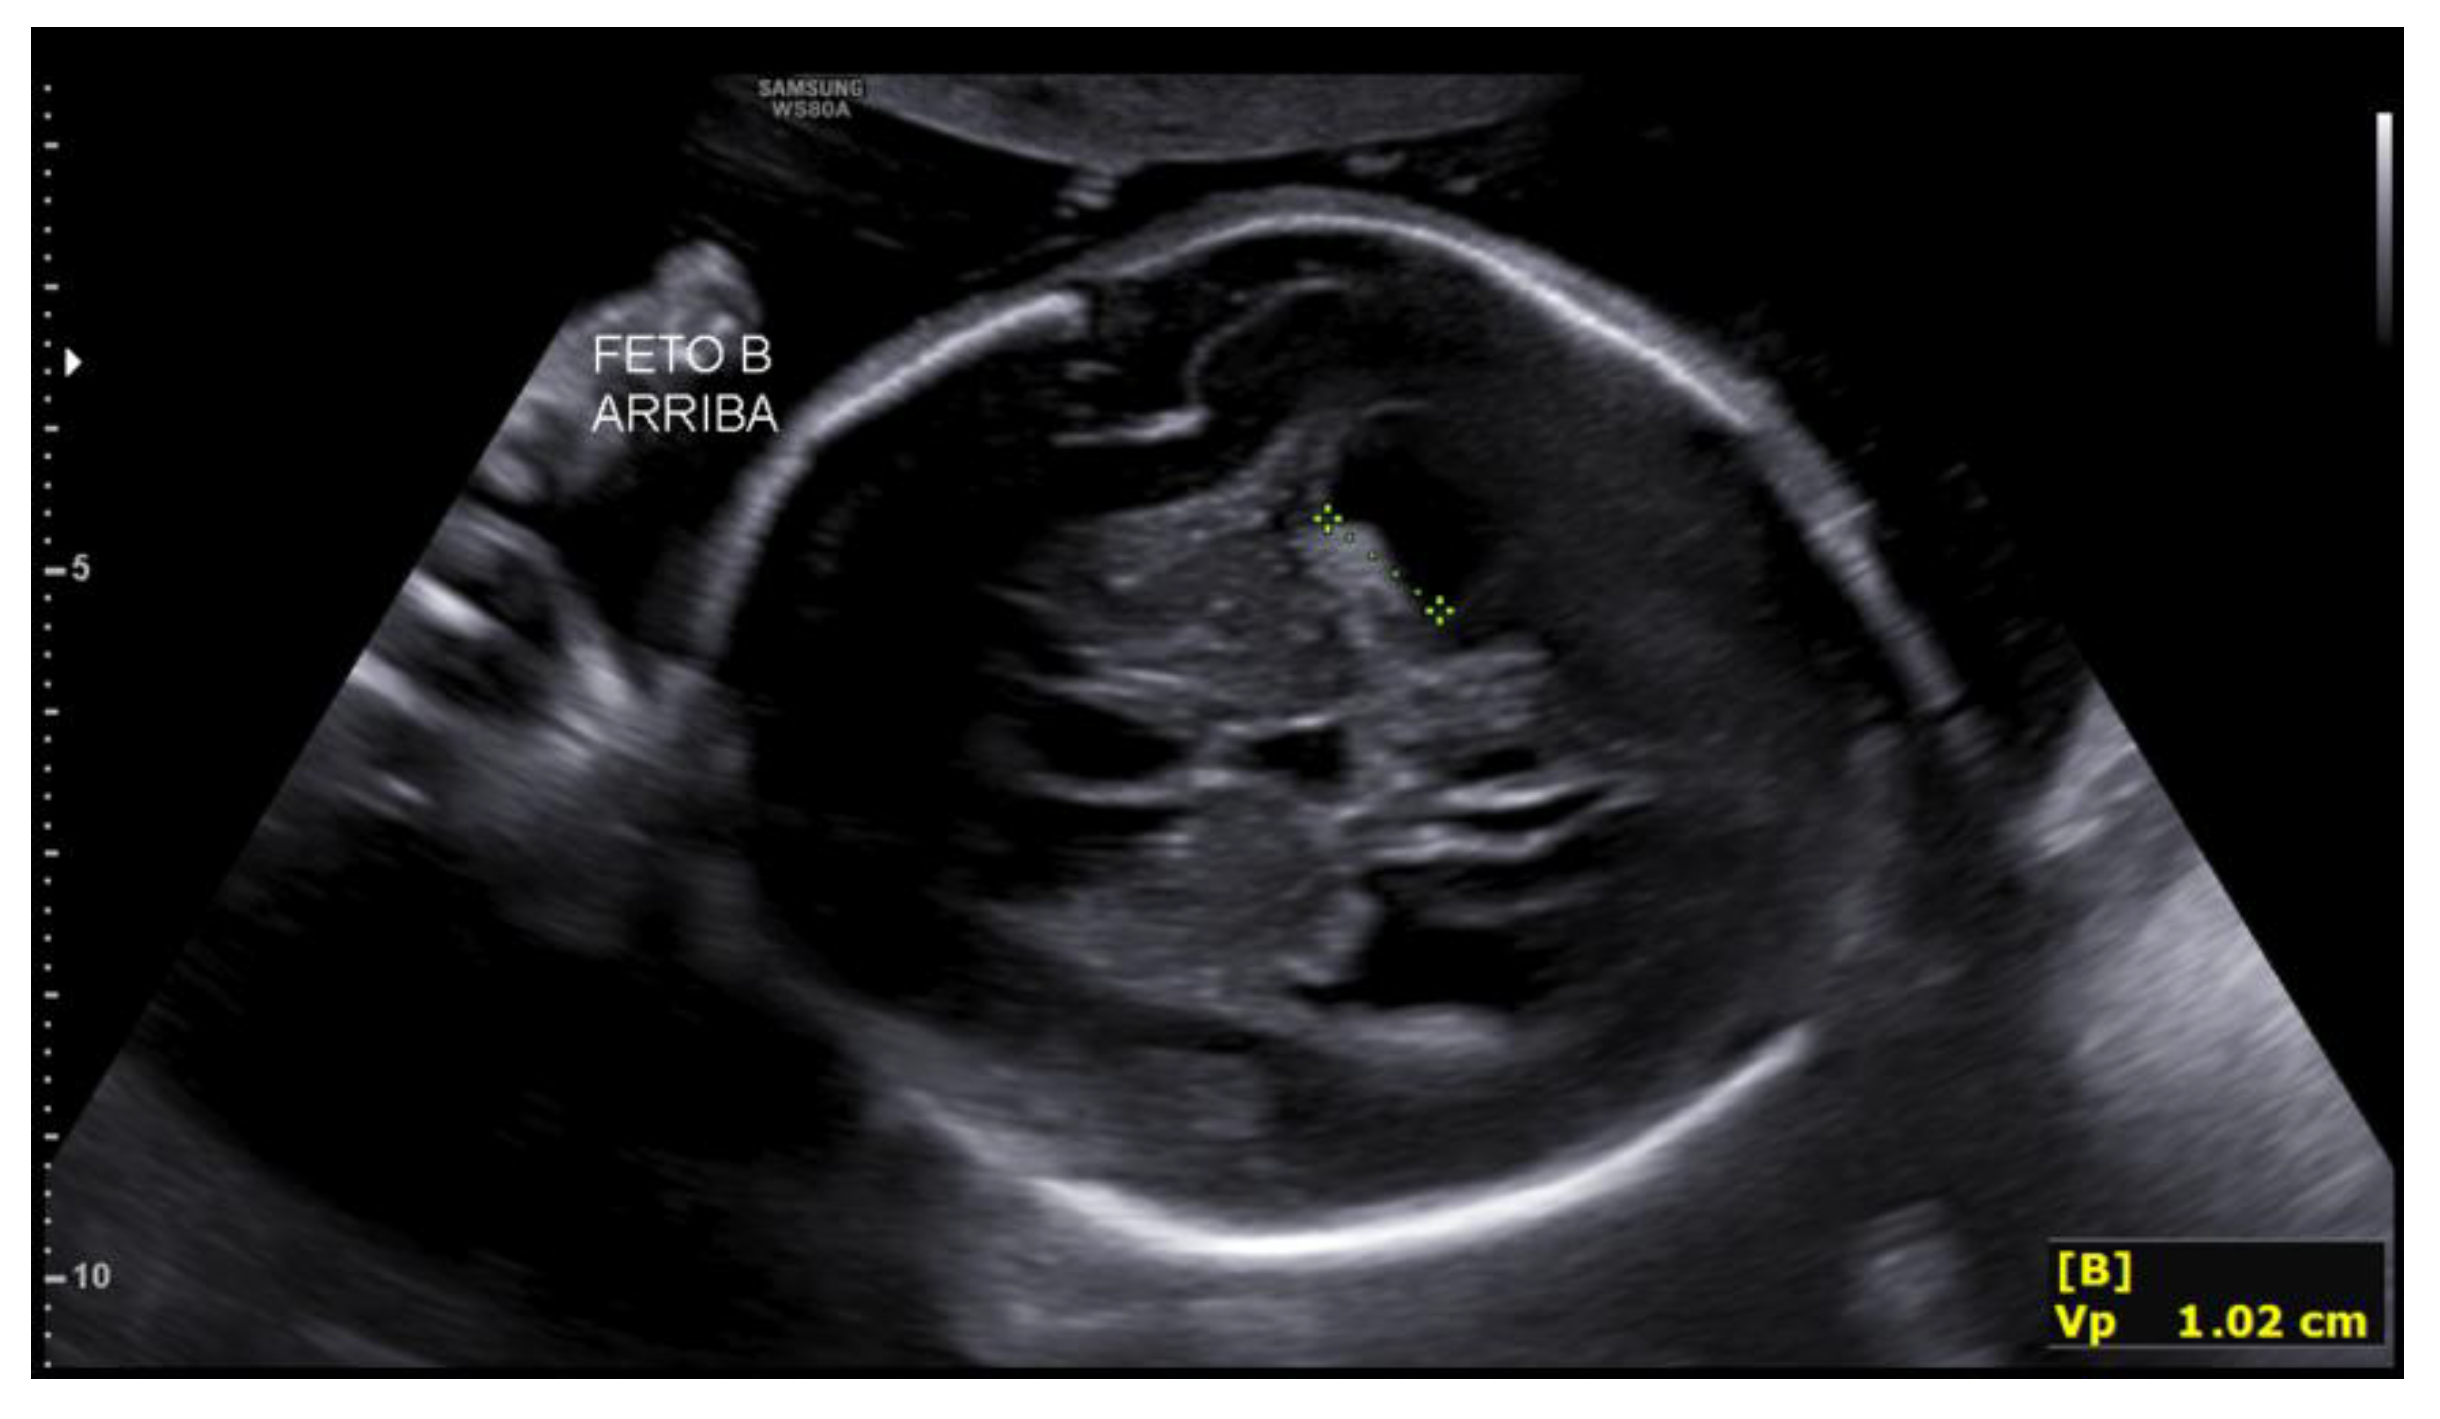

Figure 5. Rhizomelic shortening of the upper limb in the second fetus at 27+2 weeks.